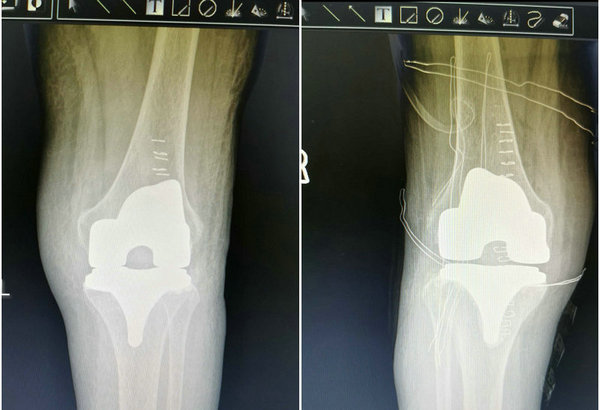

术后双膝影像检查图